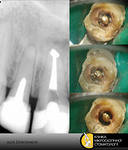

В частности Стоматологическая клиника "Аполлония" производит операцию извлечения анкерных штифтов при помощи специального микроскопа, позволяющего не только видеть процесс лечения зуба и мельчайшие микротрещины на нем, но и снимать его основные моменты на видео- и фотокамеру.

На первом этапе с больного зуба снимается коронка.

После ее удаления головка штифта достаточно хорошо просматривается.

Далее, специальными ультразвуковыми насадками, штифт извлекается из зуба всего за несколько минут и, практически, безболезненно.